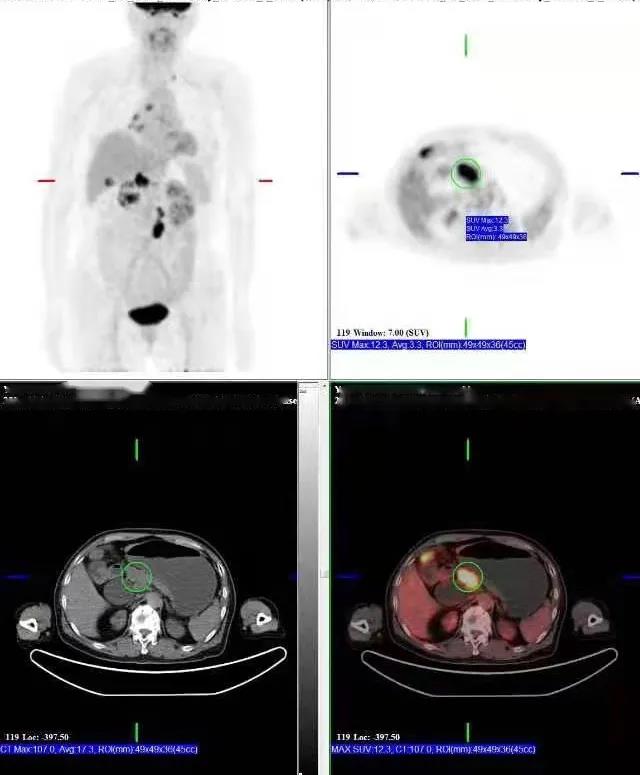

PET/CT檢查所見:胰腺鉤突見一低密度灶,動脈期及靜脈期強(qiáng)化稍低于周圍正常胰腺組織,延遲期掃描病灶與正常胰腺呈等密度,病灶邊界欠清晰,大小約2.6×3.7cm,F(xiàn)DG攝取增高,SUVmax:9.8。胰周脂肪間隙清晰,胰管未見擴(kuò)張。肝門區(qū)及腹膜后見多發(fā)腫大淋巴結(jié)影,增強(qiáng)掃描呈環(huán)形強(qiáng)化,最大者大小約2.2×3.5cm,F(xiàn)DG攝取增高,SUVmax:17.0。膽總管明顯擴(kuò)張,呈囊狀改變,最寬處約直徑4.5cm。

提示: 胰腺鉤突病變,糖代謝增高,考慮胰腺癌可能性大

肝門區(qū)及腹膜后淋巴結(jié),糖代謝增高,考慮轉(zhuǎn)移性淋巴結(jié)

先天性膽管擴(kuò)張